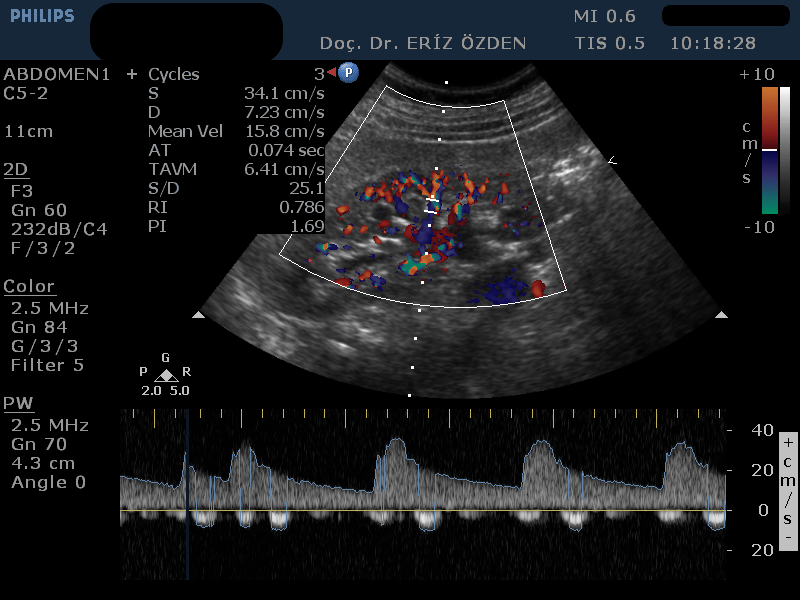

Böbreğe giden atardamarlarda darlık olması durumunda, tansiyon yüksekliği (hipertansiyon) ortaya çıkabilir. Böbrek damarlarının ayrıntılı incelenmesi, darlıkların, tıkanıkların saptanması, böbrek kanlanması hakkında bilgi edinilmesi için Renkli Doppler Ultrason kullanılır. İnceleme sırasında bağırsak gazları görüntüyü bozabileceğinden, hastanın aç olarak gelmesi gereklidir.